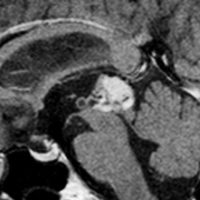

松果体細胞腫の例4(のう胞性腫瘍)

30代女性ののう胞性の松果体細胞腫です。これは大きな松果体嚢胞とほとんど画像では区別がつかないものでした。でも腫瘍ののう胞壁(液体の入っている袋の壁)の後方がガドリニウム増強されていてごく一部が実質性であることが解ります。